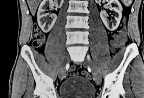

복부 CT는 X선을 사용해 배 속 장기들의 단면을 정밀하게 촬영하는 검사입니다.

초음파보다 더 넓은 부위와 깊은 장기를 볼 수 있고, 장기 구조나 종양, 염증, 출혈, 혈관 상태까지 정밀하게 진단할 수 있어요.